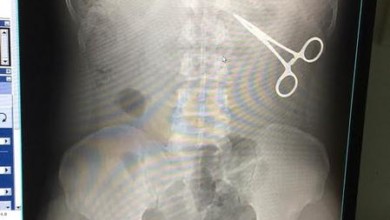

توقيف حاجّ بمطار جدة بسبب “مقص” في بطنه